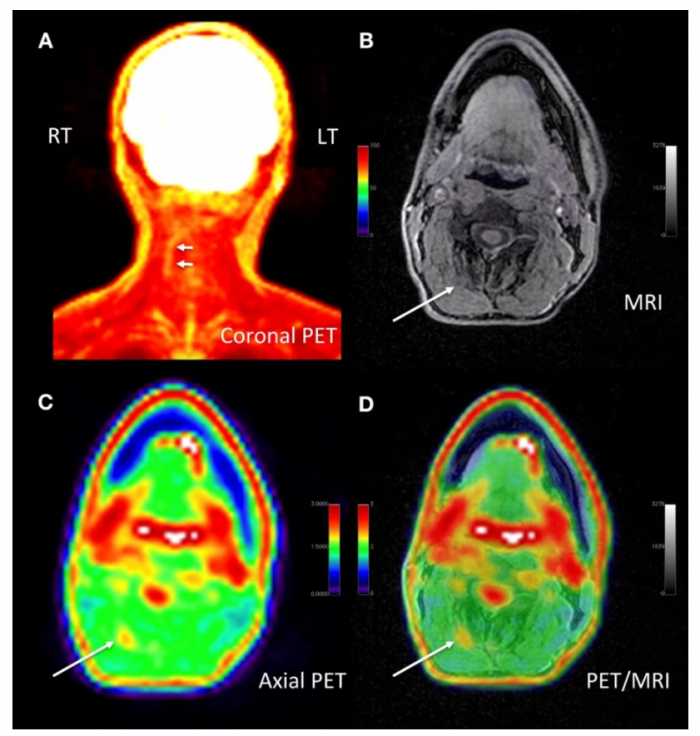

据外媒报道,在核医学与分子影像学会2020年虚拟年会上,提出了两项医学影像技术的突破。这些技术进展展示了一种PET/MRI方法来定位患者慢性疼痛的特定位置,以及一种新的全身扫描仪,可以首次可视化炎症性关节炎的完整系统负担。

数以千万计的美国人饱受慢性疼痛的折磨,然而在患者的主观反应之外,很少有诊断工具可以客观地评估其位置或严重程度。由斯坦福大学医学院的研究人员领导的一项新研究展示了一种新的PET/MRI成像方法,可以精确地确定患者慢性疼痛的确切位置。

该研究招募了65名患有慢性疼痛的受试者,并使用18F-FDG进行了全身PET/MRI扫描,以确定组织中葡萄糖摄取增加的特定位置。新颖的成像技术有效地将58名受试者的特定疼痛位置归零。随后,新的临床信息导致其中40名受试者改变了疼痛管理计划。

研究人员注意到,例如一位患者出现了数十年的慢性颈部疼痛,在多种治疗方案后仍未解决。该扫描以令人难以置信的特异性突出了FDG摄取量升高的特定位置。

根据影像学数据,一位外科医生对该处进行了探查,发现慢性疼痛的根源是一些微小的动脉收缩了神经。经过快速的外科手术,即所谓的溶解术,患者报告说,他们多年来遭受的慢性疼痛得到了显著缓解。